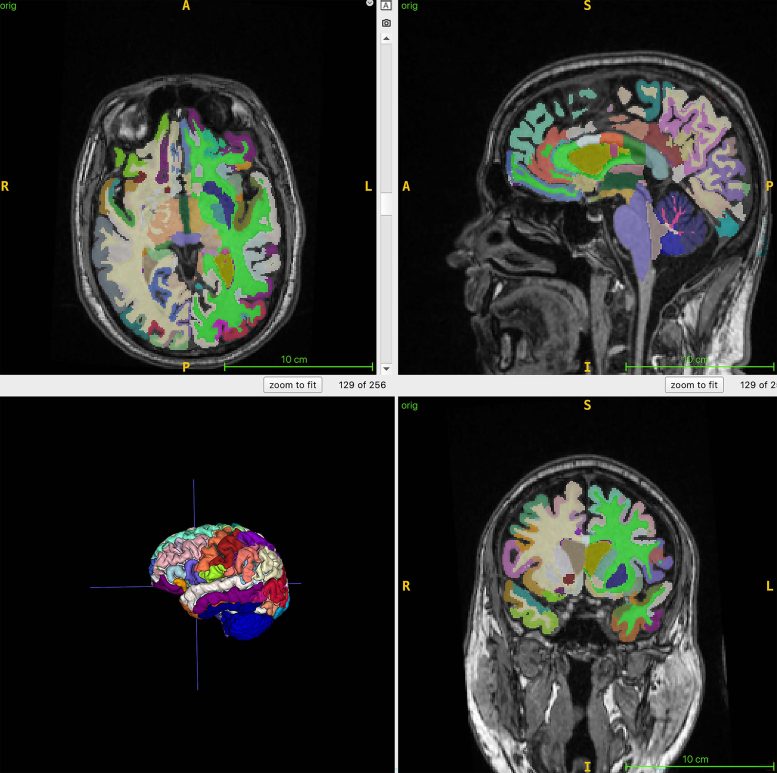

Brain age is an estimated biological age of the brain based on a structural MRI scan. Muscle mass measured through body MRI can serve as an indicator for interventions aimed at reducing frailty and supporting brain health, while brain age calculated from structural images may help identify Alzheimer’s disease risk factors, including muscle loss.

In the ongoing research, whole-body MRI scans were performed on 1,164 healthy adults (52% women) across four locations. The average chronological age of the group was 55.17 years. The team used MRI with T1-weighted sequences, which highlight fat as bright and fluid as dark, allowing clear visualization of muscle, fat, and brain tissue. An artificial intelligence (AI) tool then measured total normalized muscle volume, visceral fat (hidden belly fat), subcutaneous fat (fat under the skin) and brain age.